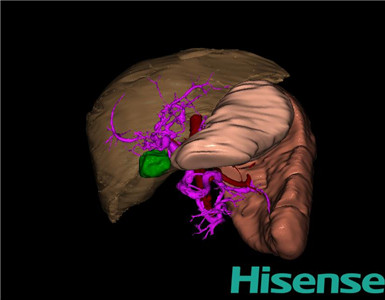

CT结果输入海信CAS系统后行3D重建及手术规划后,行手术治疗,术中证实为先天性门脉高压:

术前三维重建及手术方案设计:

将0.625mm双源薄层CT资料的静脉期和动脉期Dicom格式文件导入海信CAS系统。

通过调节窗宽窗位调整CT序号,对肝实质,胆囊,下腔静脉,肿瘤,肝动脉、门静脉及肝静脉等进行三维重建;系统自动计算肝脏体积。

术前三维重建:

重建图片